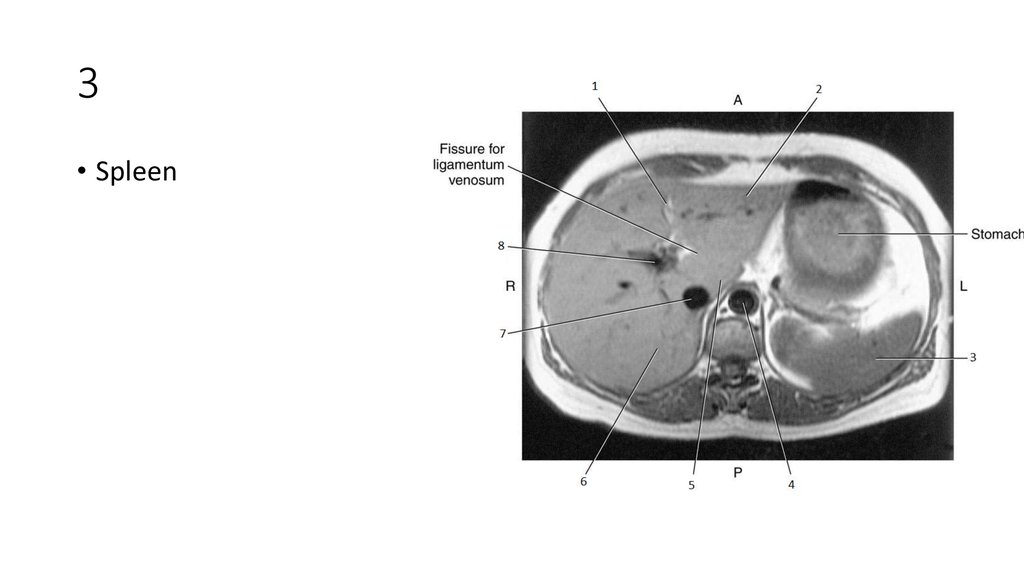

20. 3

21. 3

• Spleen